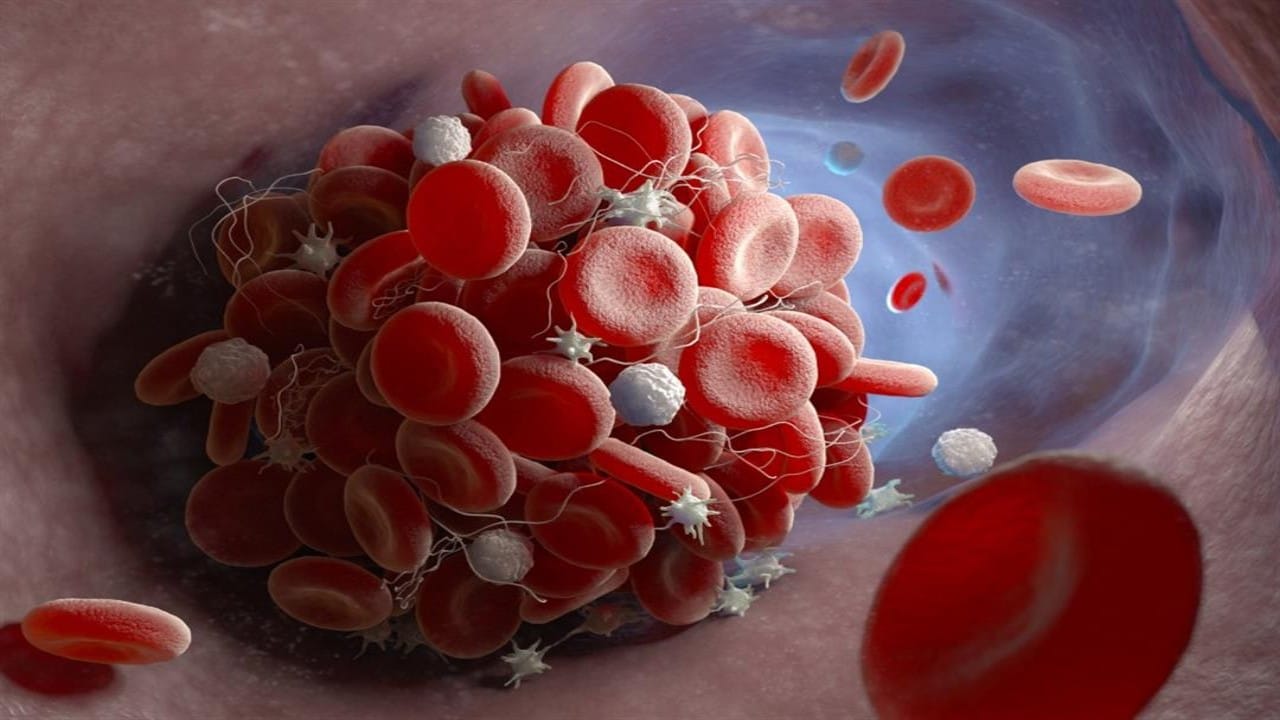

أعراض للجلطات تظهر فجأة وتسبب الوفاة

منذ 2 سنة

0

2062

أطعمة ومشروبات تزيد خطر الإصابة بالجلطات الدموية

منذ 2 سنة

0

1223